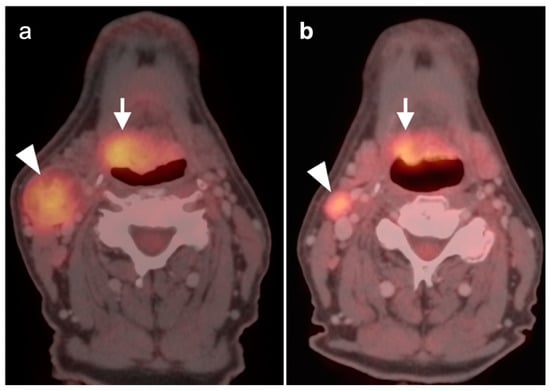

2.5. Major and Minor Salivary Gland, Lacrimal Gland Tumors

- Warthin tumor